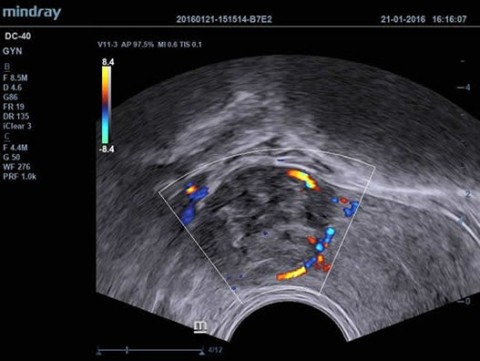

Аппарат ультразвуковой диагностический DC-40

Аппарат ультразвуковой диагностический DC-40 - 393 400 руб.

- Режимы сканирования B/M/Цветовой доплер CDI/Цветной M/Энергетический доплер PD/Направленный энергетический доплер Dir.PD

- Shared Service (включая пакеты Obstetrics, Pediatrics, Gynecology, Abdomen, Urology, Small Parts, Vascular and Cardiology packages)

Применение УЗИ:

Общая диагностика, Кардиология